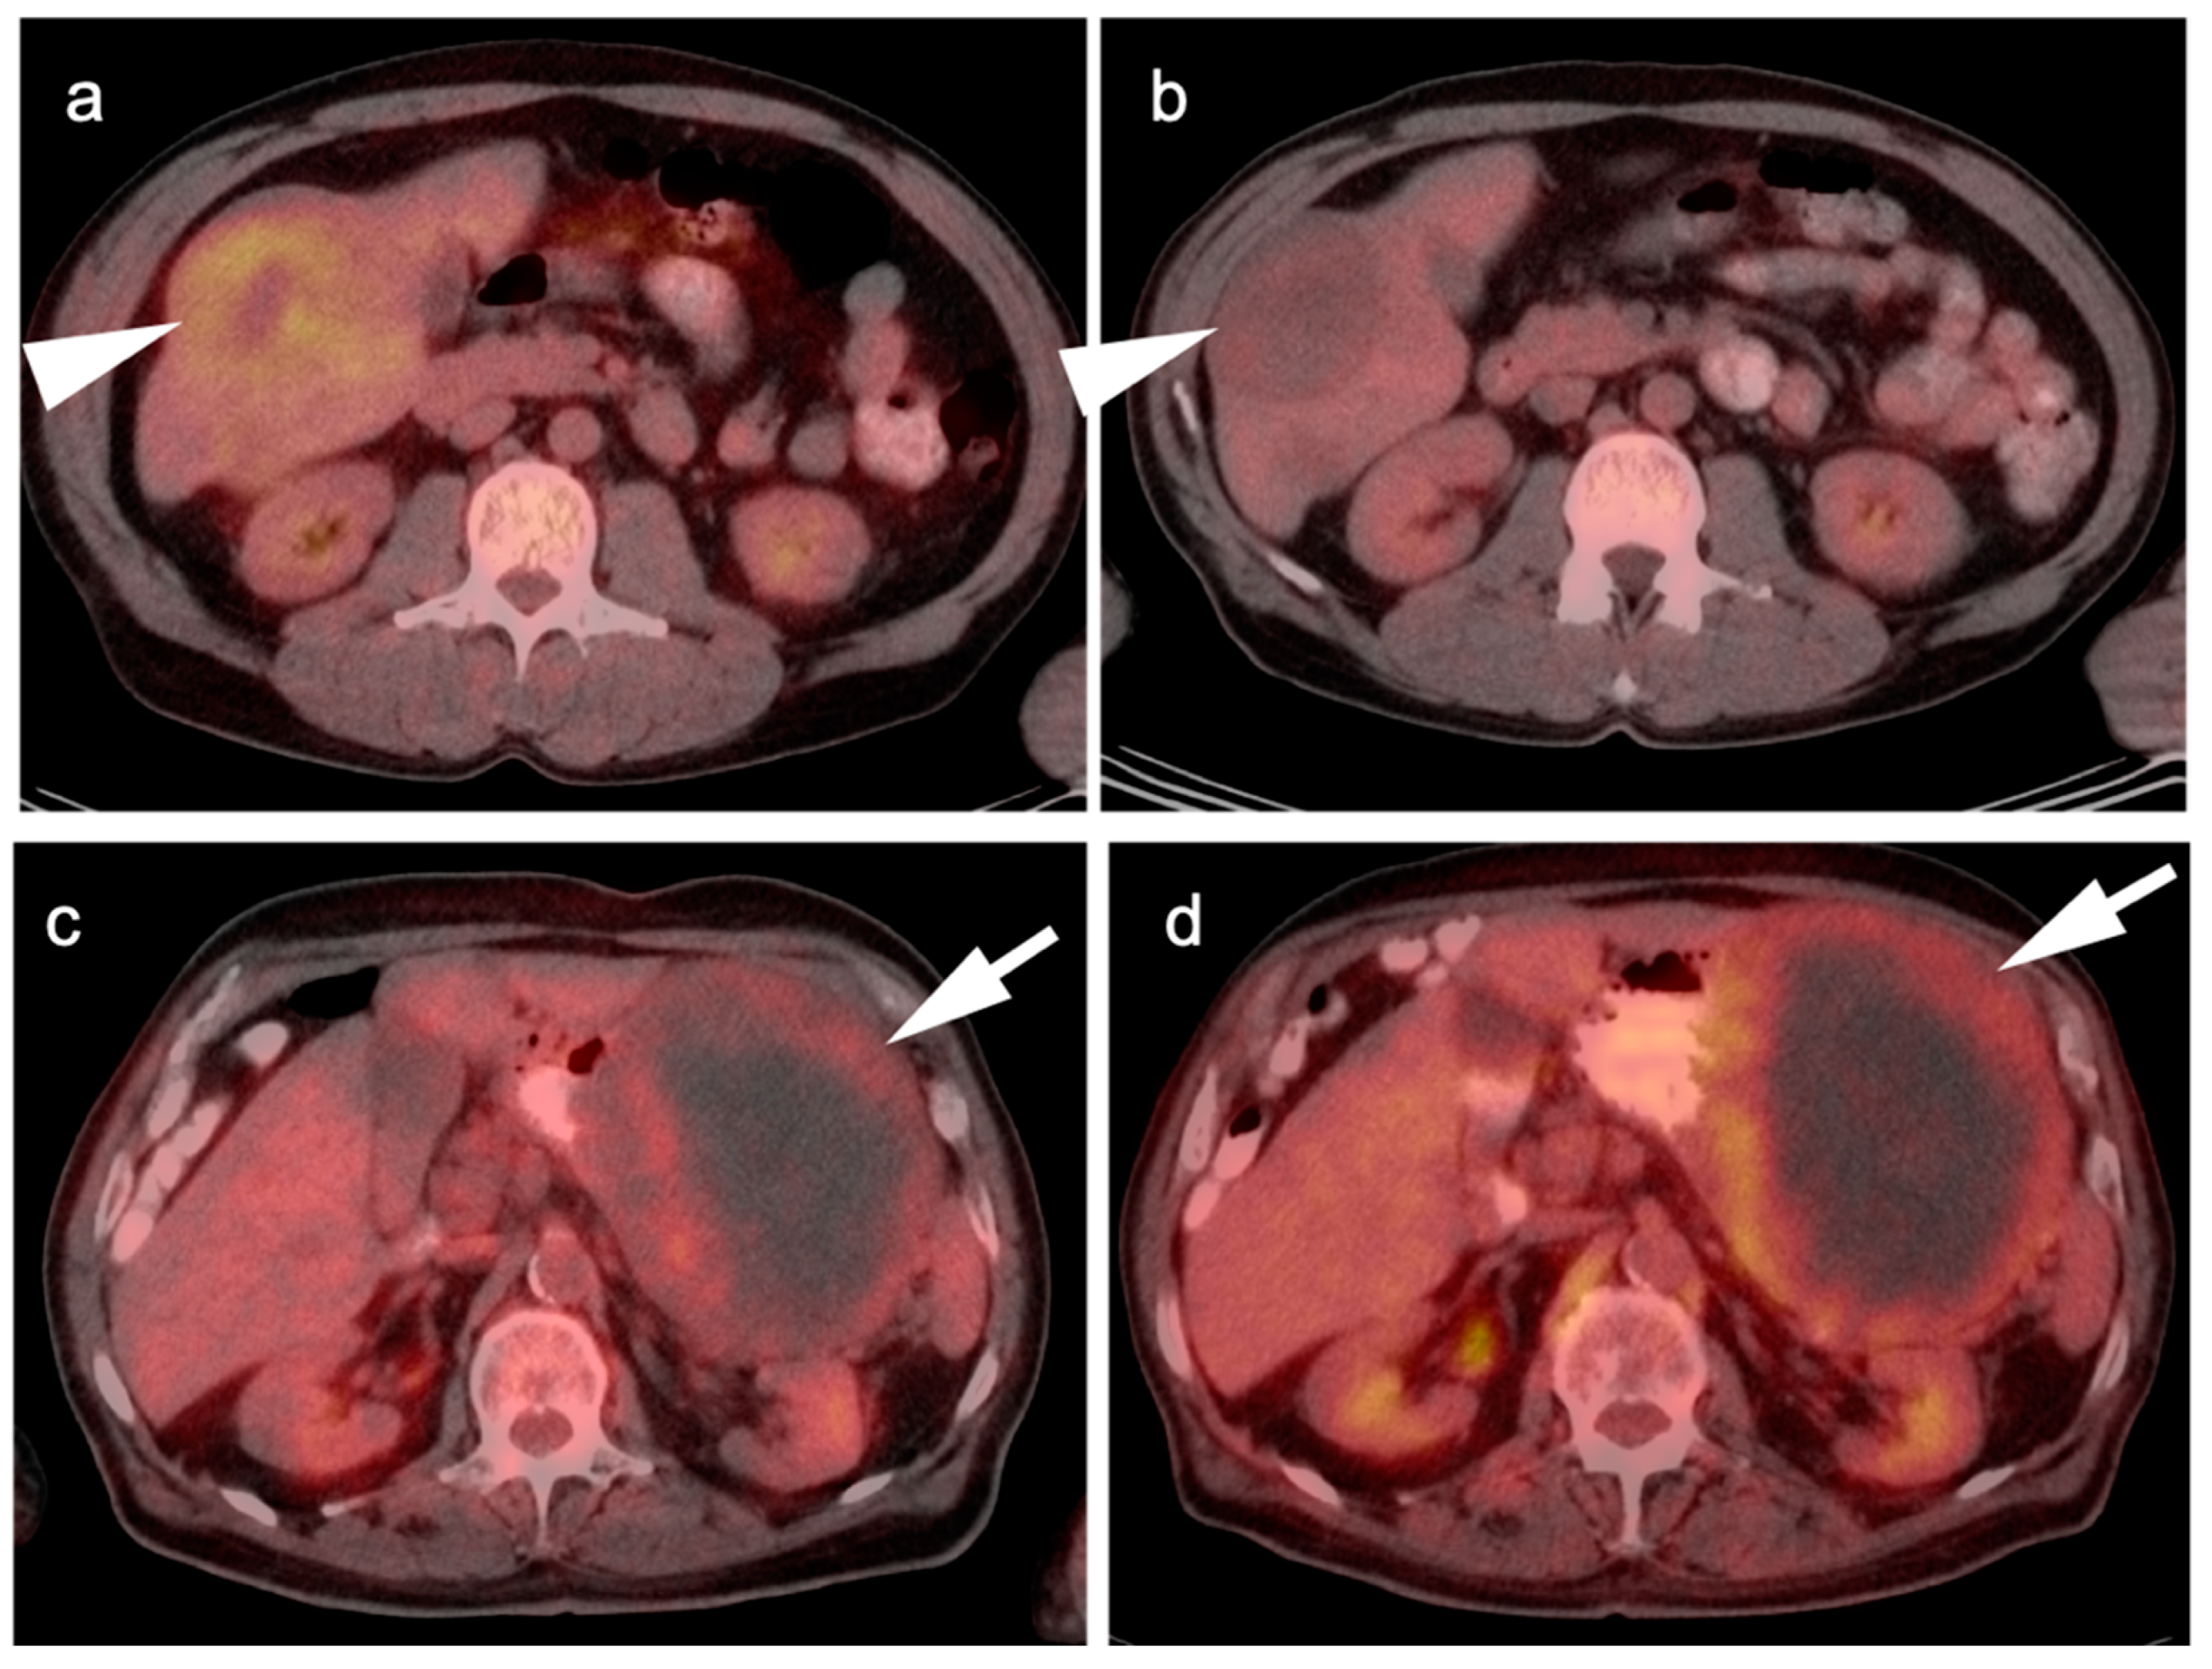

- Van den Abbeele, A.D. The Lessons of GIST—PET and PET/CT: A New Paradigm for Imaging. Oncologist 2008, 13 (Suppl. 2), 8–13. [Google Scholar] [CrossRef]

- Holdsworth, C.H.; Badawi, R.D.; Manola, J.B.; Kijewski, M.F.; Israel, D.A.; Demetri, G.D.; Van den Abbeele, A.D. CT and PET: Early Prognostic Indicators of Response to Imatinib Mesylate in Patients with Gastrointestinal Stromal Tumor. AJR Am. J. Roentgenol. 2007, 189, W324–W330. [Google Scholar] [CrossRef]